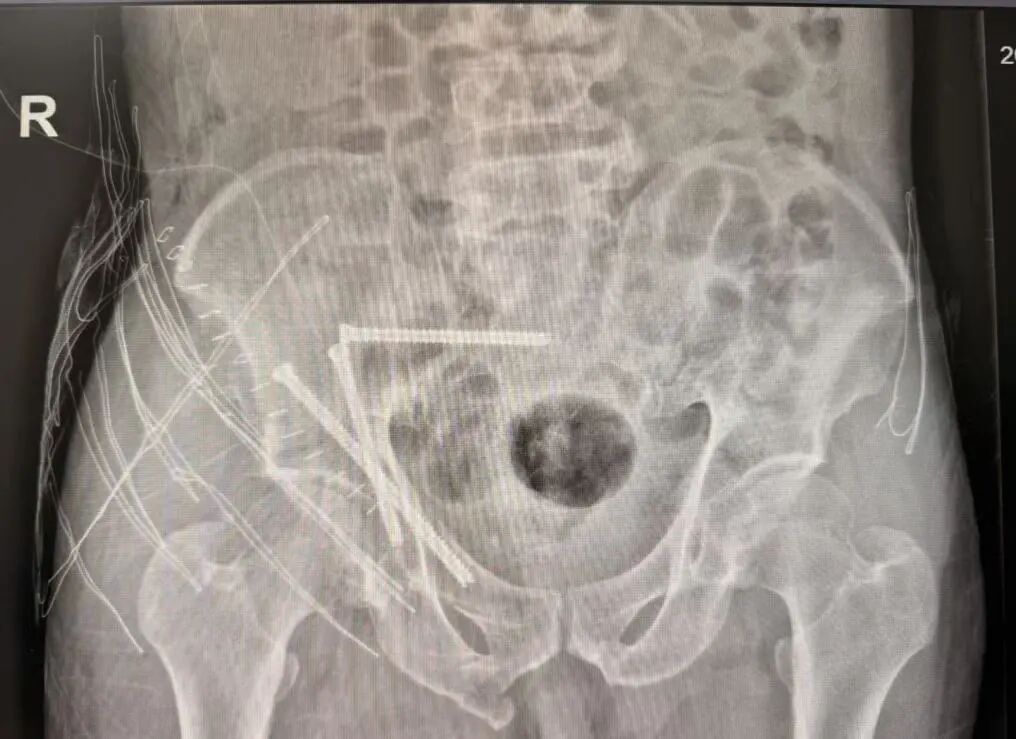

术前

团队通过三维影像重建,为患者量身定制手术路径,数据导入系统后生成个性化复位方案。

术中

机械臂按预设路径自动执行复位操作,精度高达毫米级,医生仅需通过几个微小切口置入内固定螺钉。